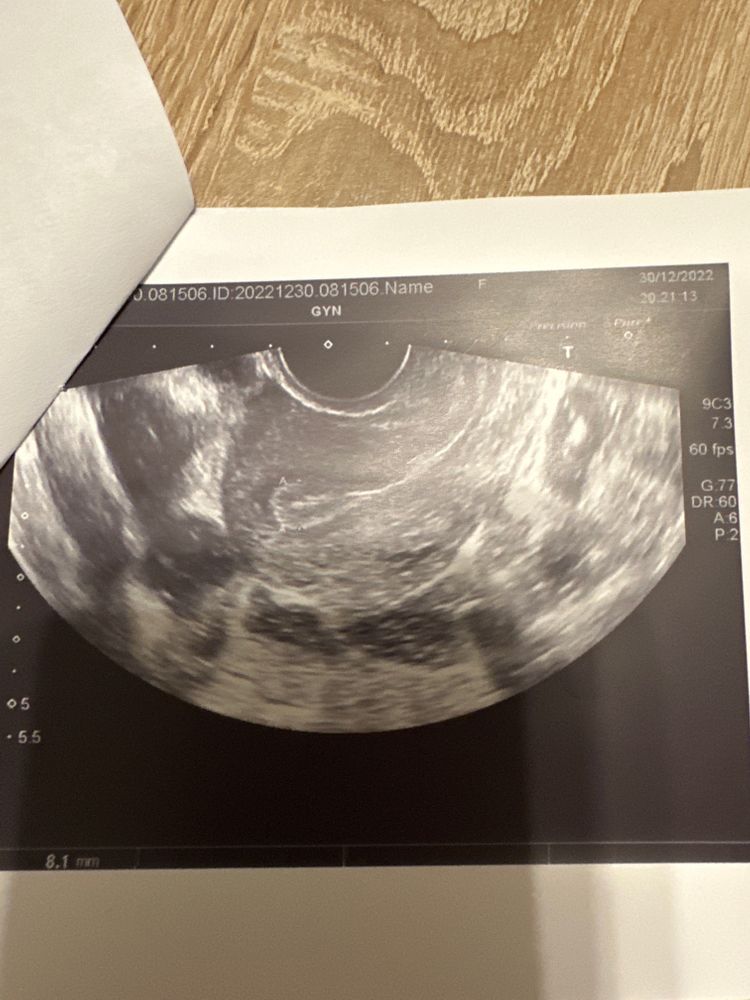

врача очень смущает эндометрий, который есть только в одной части (фото приложу).

Как видно, только есть только треть эндометрия. Гинеколог предположила что остальная часть сильно повреждена